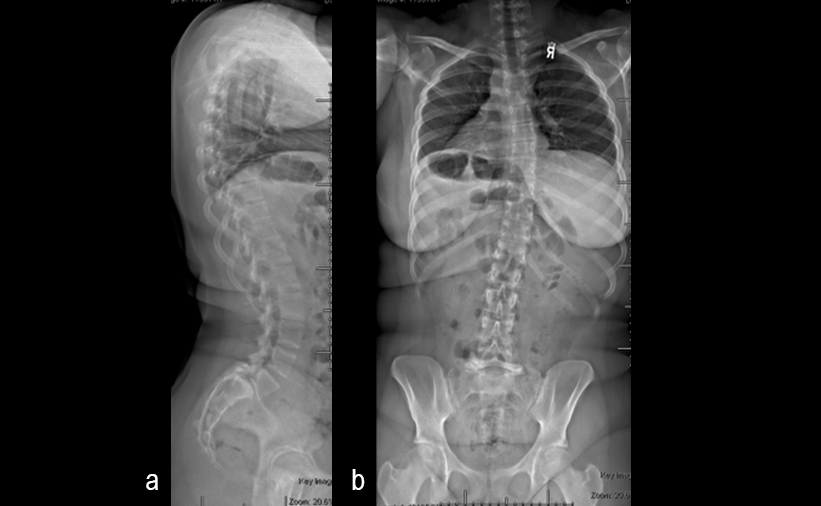

A 17-year-old girl presented to the spine clinic with significant low back pain. X-ray, CT and MRI imaging (Figs 1-3) showed evidence of spondylolisthesis. Upon clinical examination of spinal alignment, the patient was found to have a pelvic incidence of 78°, a lumbar lordosis of 54°, and a pelvic tilt of 51°.